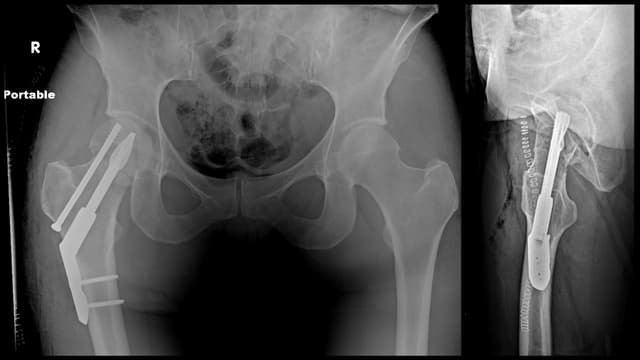

Femoral Neck ORIF

Post-op